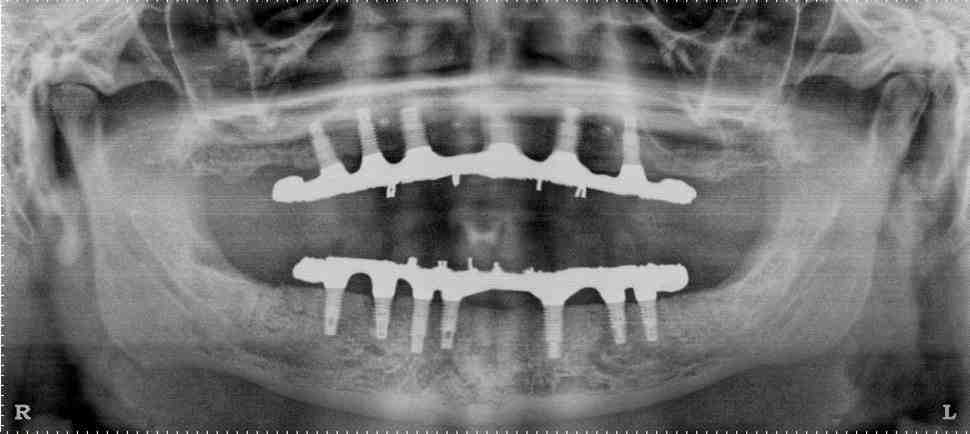

How many implants are needed for full mouth?